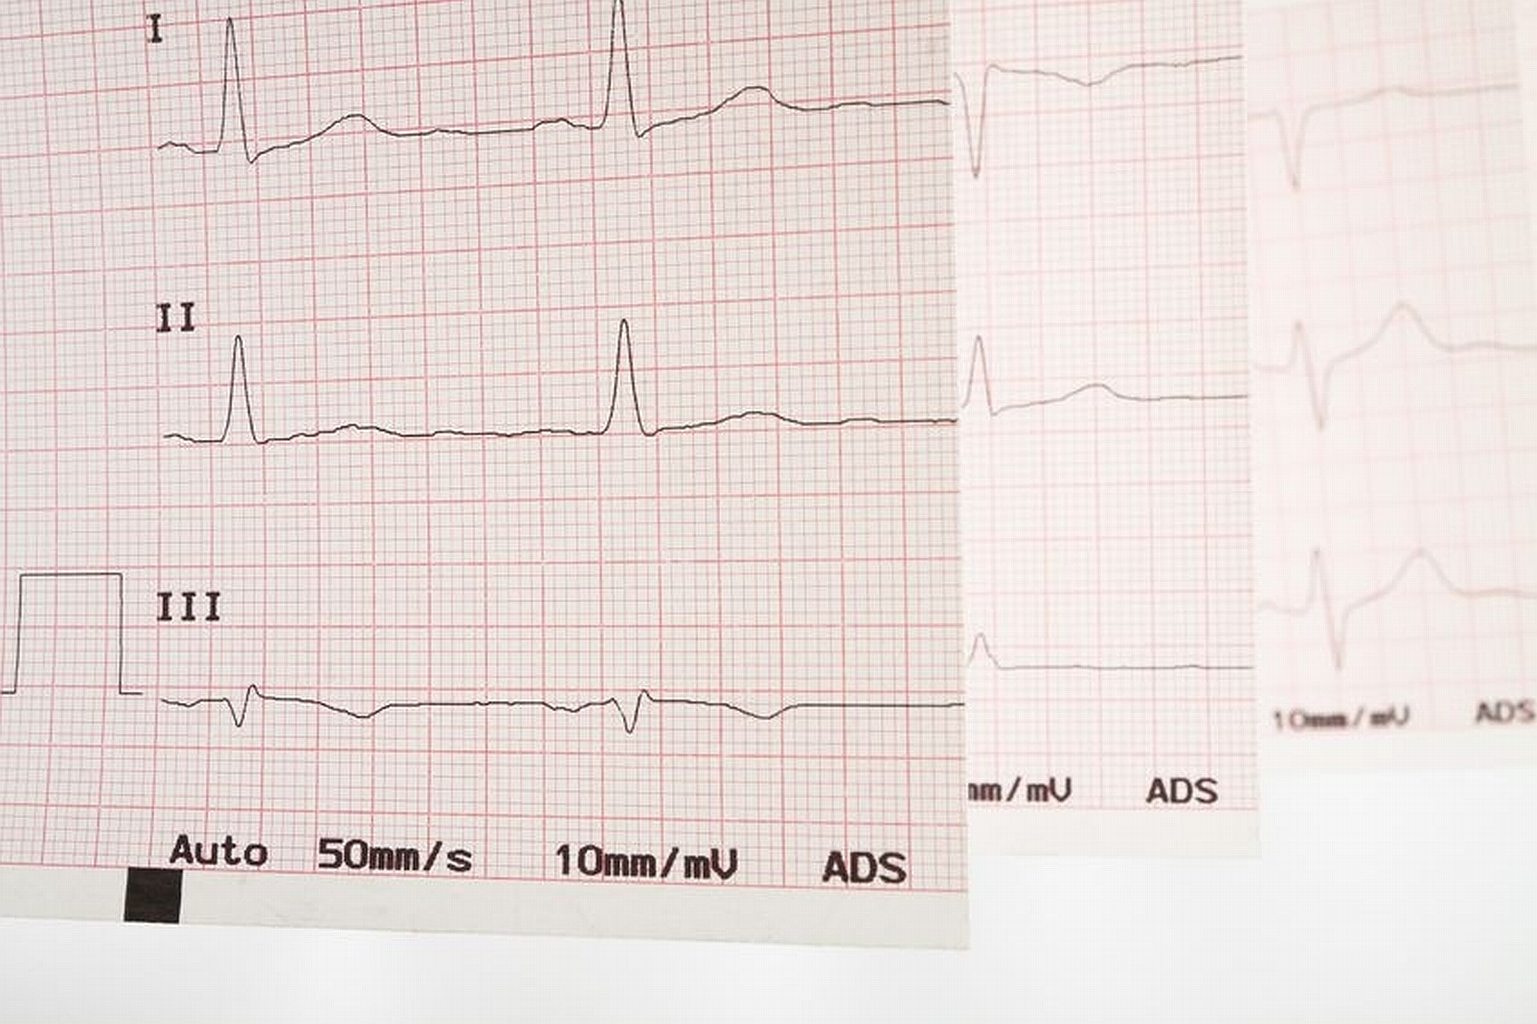

Powody niemiarowego bicia serca może wyjaśnić badanie EKG, lecz nie uchodzi ono za standard w gabinetach lekarzy rodzinnych. Powody niemiarowego bicia serca może wyjaśnić badanie EKG, lecz nie uchodzi ono za standard w gabinetach lekarzy rodzinnych. maurus / Smarterpix/PantherMedia

Spośród 400 tys. chorych co czwarty nawet nie wie, że powinien się leczyć (powody niemiarowego bicia serca i częstego zmęczenia może wyjaśnić badanie EKG, lecz nie uchodzi ono przecież za standard w gabinetach lekarzy rodzinnych). Dlatego z terapii korzysta raptem 215 tys. chorych, z których mniej niż 10 tys. leczy się nowoczesnymi preparatami. 160 tys. stosuje leki przeciwkrzepliwe starszej generacji, choć u 60 proc. tzw. współczynnik krzepliwości balansuje na granicy normy i w każdej chwili może wystąpić u nich niebezpieczny krwotok. Na tym polega trudność tej terapii: z jednej strony trzeba zabezpieczać chorego przed powstającymi wskutek migotania zakrzepami, z drugiej – nie dopuszczać do zbytniego rozrzedzenia krwi i zagrożenia krwawieniami. Niektórzy nie chcą podejmować tego ryzyka, więc się nie leczą – a sporadyczny kontakt z lekarzem w przychodni nie pozwala na to, by wyjaśnić wątpliwości i dobrać bezpieczną kurację.